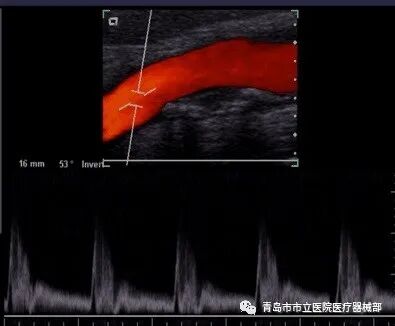

3.4.4彩色血流成像(CFM

彩色多普勒血流显像(CDFI)或彩色多普勒显像(CDI)主要是利用血液中运动的红细胞对声波的散射,产生多普勒效应,经伪彩色编码技术,在二维图像上显示彩色血流影像。其与脉冲多普勒一样的原理,不同的是脉冲多普勒表示一小段深度的血流速度随时间的变化;而CFM法是用色彩来表示沿接收信号声束多个部位(深度)的血流速度,并叠加在B超图像上,其特征是可以发现异常血流(反流、动静脉短路等)。CFM法显示主要分为速度显示法、速度-离散显示法。

速度显示法:血流方向由红色(朝向探头的血流)、蓝色(远离探头的血流)来表示。速度快慢由红色变为黄色、蓝色变为蓝绿色的色彩变化来表示。

速度-离散显示法:血流方向由红色、蓝色来表示,速度快慢由不同颜色的亮度来表示,速度紊乱(分散)以绿色来表示,能清楚显示瓣膜反流等快速血流,主要应用于循环系统检查。